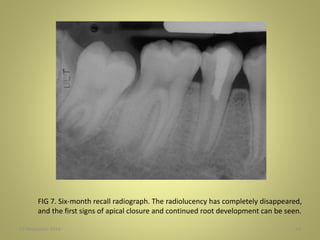

FIG 7. Six-month recall radiograph. The radiolucency has completely disappeared,

and the first signs of apical closure and continued root development can be seen.

27 November 201654 FIG 7. Six-month recall radiograph. The radiolucency has completely disappeared, and the first signs of apical closure and continued root development can be seen.